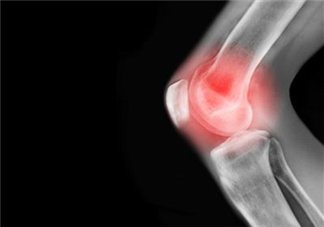

關(guān)節(jié)炎泛指發(fā)生在人體關(guān)節(jié)及其周圍組織的炎性疾病,可分為數(shù)十種。我國(guó)的關(guān)節(jié)炎患者有1億以上,且人數(shù)在不斷增加。臨床表現(xiàn)為關(guān)節(jié)的紅、腫、熱、痛、功能障礙及關(guān)節(jié)畸形,嚴(yán)重者導(dǎo)致關(guān)節(jié)殘疾、影響患者生活質(zhì)量。